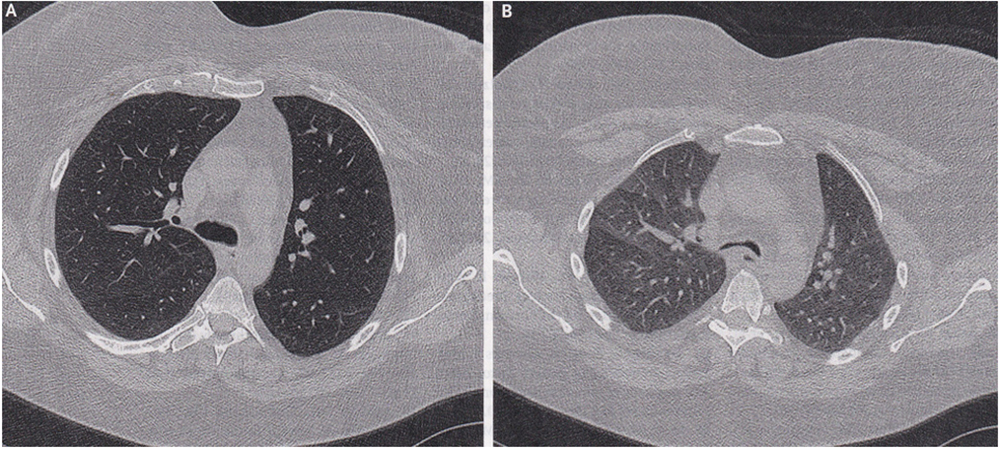

A 50-year-old woman with a history of asthma, obstructive sleep apnea, and obesity was referred to the pulmonary clinic at the University of Iowa Hospitals and Clinics in Iowa City with a one-month history of worsening shortness of breath and dry cough despite maximum treatment for asthma. On physical examination, expiratory stridor (a high-pitched noise usually caused by airway obstruction) and reduced breath sounds throughout the chest were noted. Dynamic computerized tomography (CT scan) of the chest – a study of the airway during different phases of respiration – showed anterior bowing of the posterior wall of the intrathoracic (in the chest) trachea and mainstem bronchi on expiration, with more than 70% collapse as compared to inspiration (Panel A, inspiration; Panel B, expiration, airway in the center of both images). A diagnosis of expiratory central airway collapse – a condition characterized by pathologic collapse of the central airways during expiration, resulting in dynamic outflow obstruction – was made.